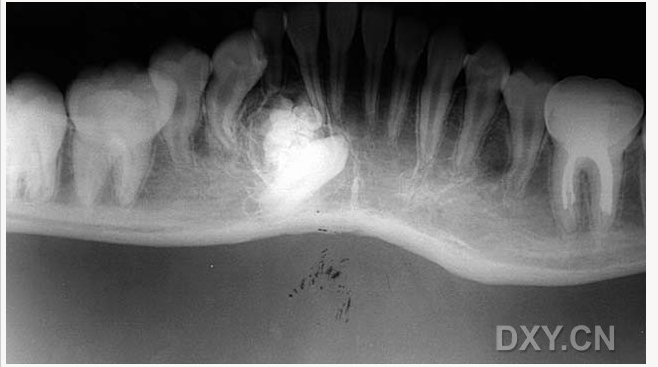

良性成牙骨質(zhì)細胞瘤